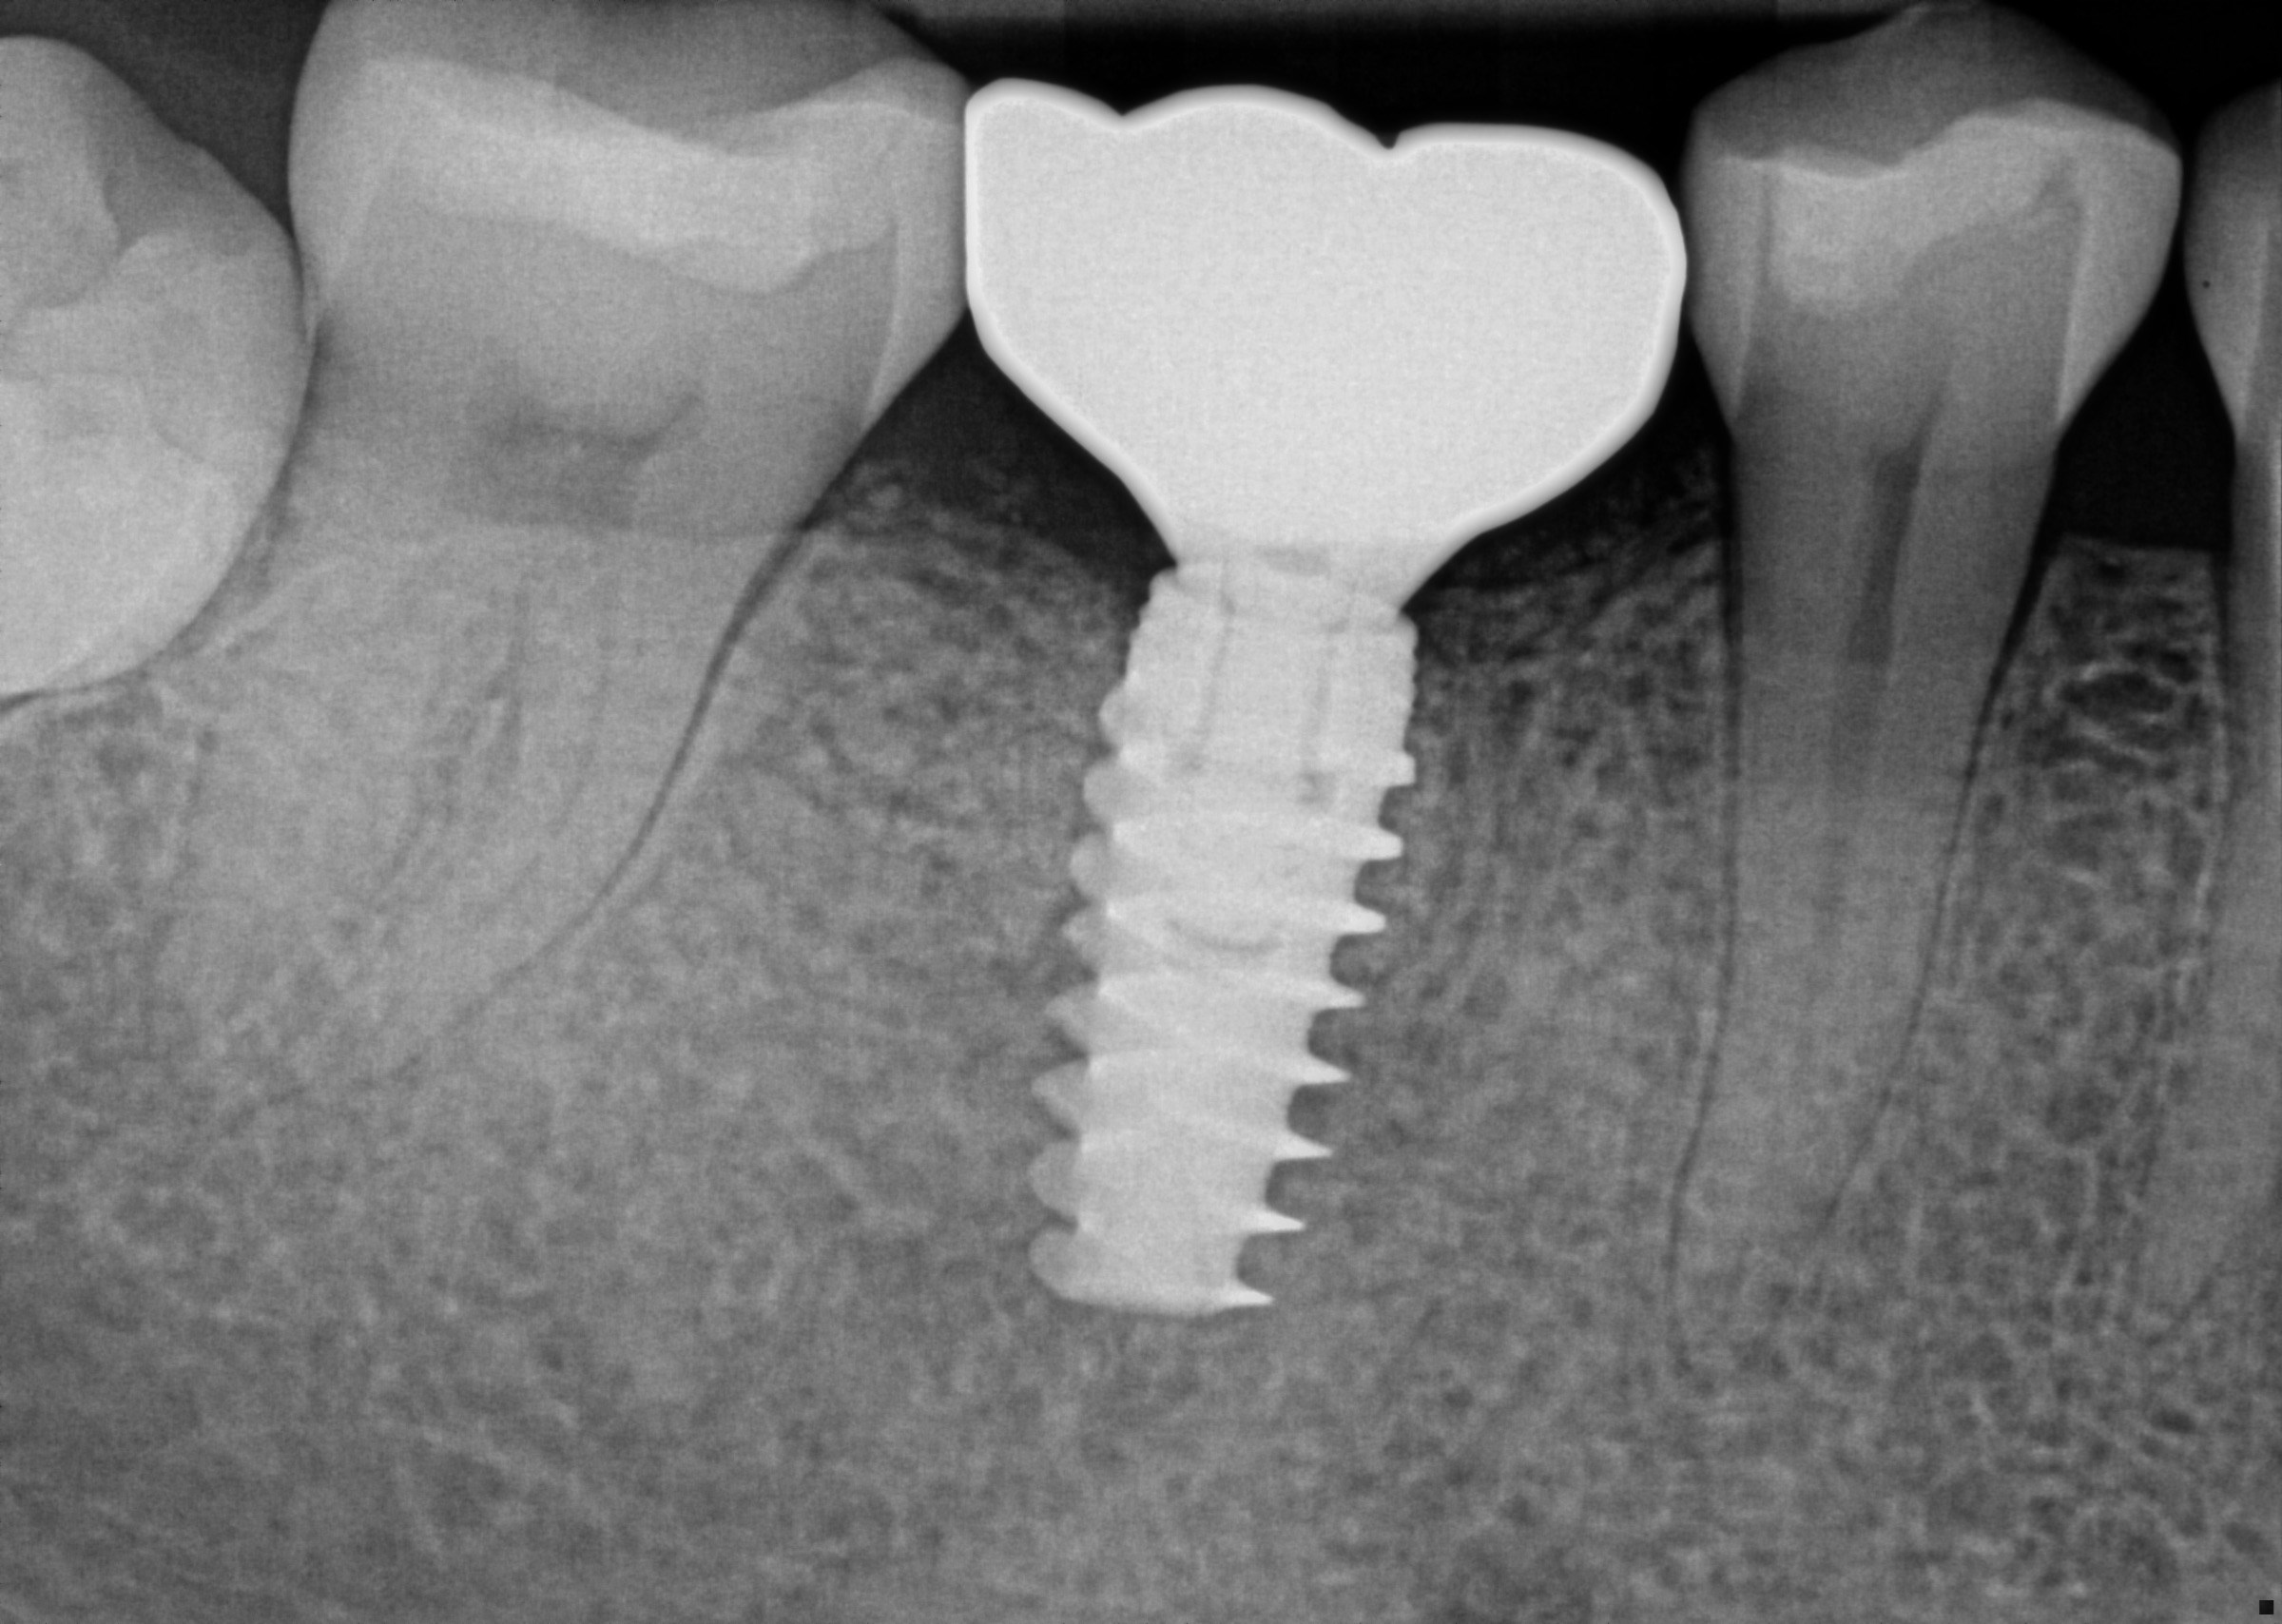

Custom Implant Crown

Procedure Details